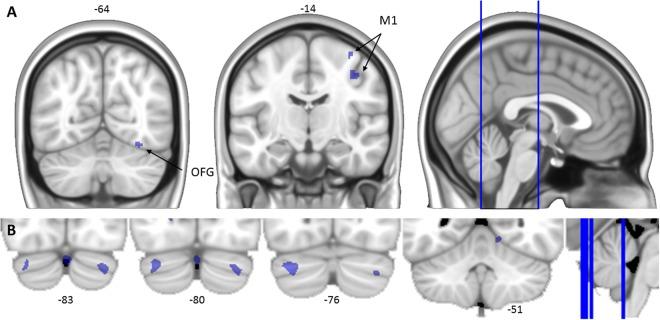

In the present study we evaluated changes in neural activation that occur over the time course of multiple days of sensorimotor adaptation, and identified individual neural predictors of adaptation and savings magnitude. We collected functional MRI data while participants performed a manual adaptation task during four separate test sessions over a three-month period. This allowed us to examine changes in activation and associations with adaptation and savings at subsequent sessions. Participants exhibited reliable savings of adaptation across the four sessions. Brain activity associated with early adaptation increased across the sessions in a variety of frontal, parietal, cingulate, and temporal cortical areas, as well as various subcortical areas. We found that savings was positively associated with activation in several striatal, parietal, and cingulate cortical areas including the putamen, precuneus, angular gyrus, dorsal anterior cingulate cortex (dACC), and cingulate motor area. These findings suggest that participants may learn how to better engage cognitive processes across days, potentially reflecting improvements in action selection. We propose that such improvements may rely on action-value assignments, which previously have been linked to the dACC and striatum. As correct movements are assigned a higher value than incorrect movements, the former are more likely to be performed again.